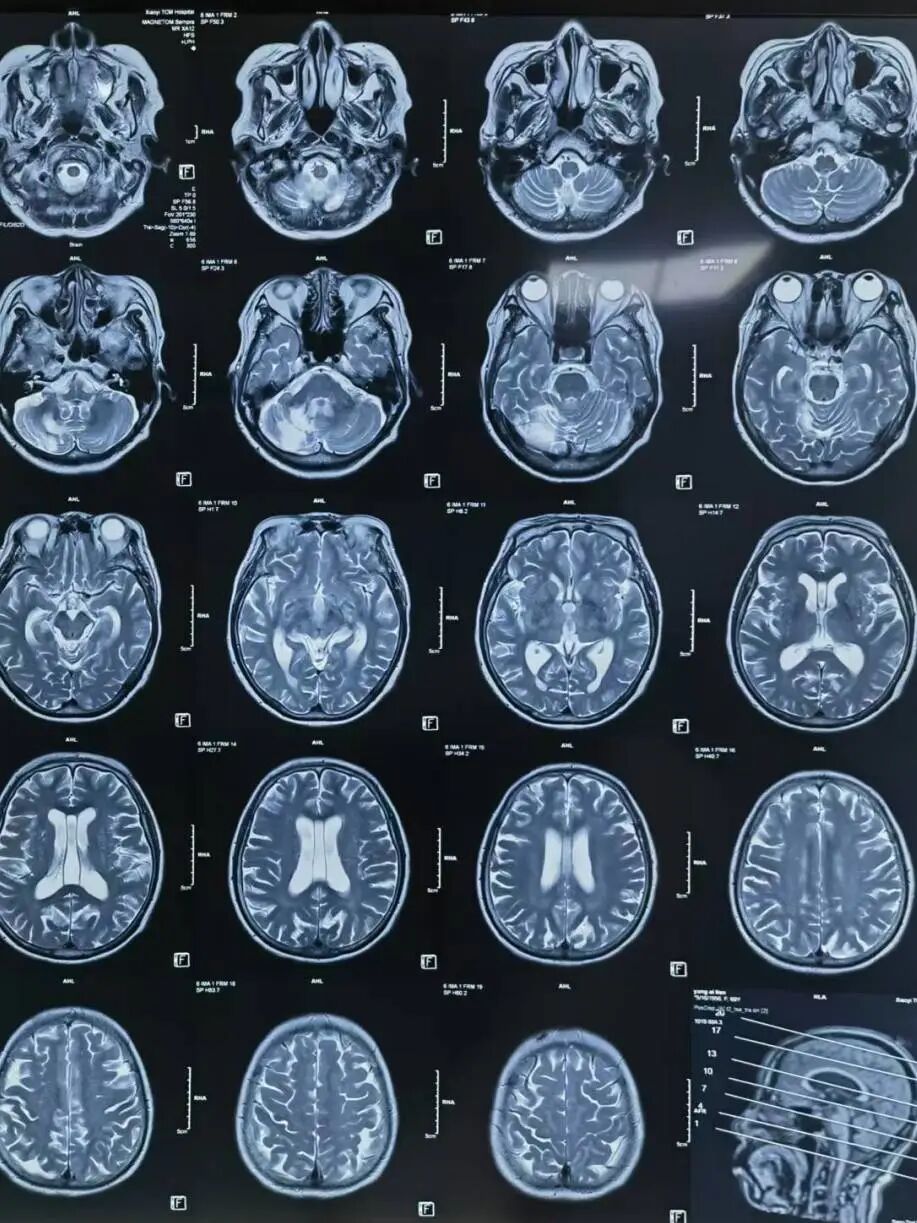

辅助检查:颅脑MR(当地医院):左侧小脑半球、双侧侧脑室旁、基底节区及双侧额叶皮层下多发腔隙性脑梗死;右侧小脑半球软化灶血管造影(当地医院)。颅脑MRA(当地医院):左侧颈内动脉后交通段局部膨大,可疑动脉瘤。 脑血管造影(当地医院) :左侧后交通动脉瘤。

颅脑MR (当地医院) :左侧小脑半球、双侧侧脑室旁、基底节区及双侧额叶皮层下多发腔隙性脑梗死;右侧小脑半球软化灶。

颅脑MRA(当地医院):左侧颈内动脉后交通段局部膨大,可疑动脉瘤。

术后颅脑CT示:颅内动脉瘤栓塞术后改变,右侧小脑半球软化灶。